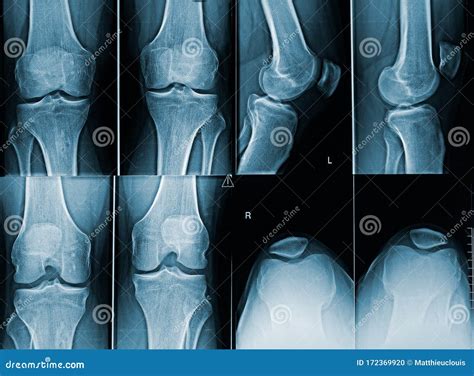

• normal knee x ray anatomy

• normal knee function x ray

• knee x ray view normal